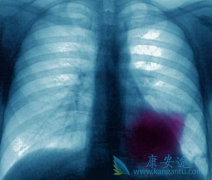

长期胸痛很可能是你已患上肺癌晚期的征兆

肺癌是目前我国发病情最高的癌症肿瘤疾病,很多肺癌患者由于一些不健康的生活习惯,如抽烟喝酒熬夜等等导致了我们的肺癌。但是由于早期肺癌几乎没有什么特别明显的症状很容易被人忽视所以也就导致了晚期肺癌,那么晚期肺癌出现的症状有哪些呢?有些肺癌 ...